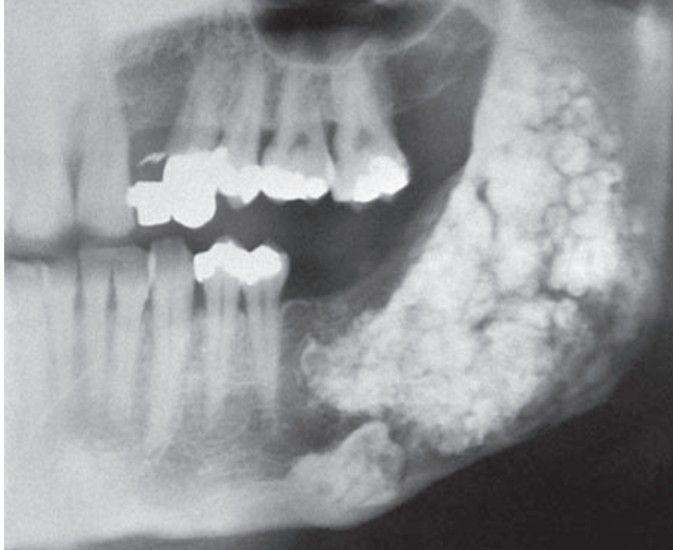

Odontoma

Complex odontoma occupying most of the mandibular ramus.